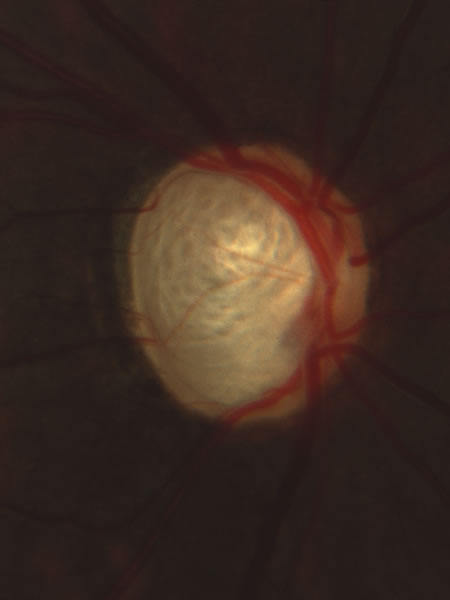

In acute angle-closure glaucoma (Fig. 33), the optic disc may swell,147–149 perhaps as a result of ischemia, but because of corneal edema and preoccupation with the angle status, it is not often seen. Even after an attack lasting several days, there is often no visual loss; the disc may remain normal appearing or may develop some degree of pallor resembling that of nonglaucomatous optic atrophy.150–152 Excavation of the disc does not seem to result from an acute attack but may result from persistent residual pressure elevation after the attack. If excavation is already present at the time that a patient presents with symptomatic angle closure, the cupping is evidence that for some time an asymptomatic, perhaps gradual, rise of intraocular pressure elevation preceded the abrupt onset of symptoms.

Fig. 33. Swollen disc tissue during an acute attack of angle closure glaucoma.